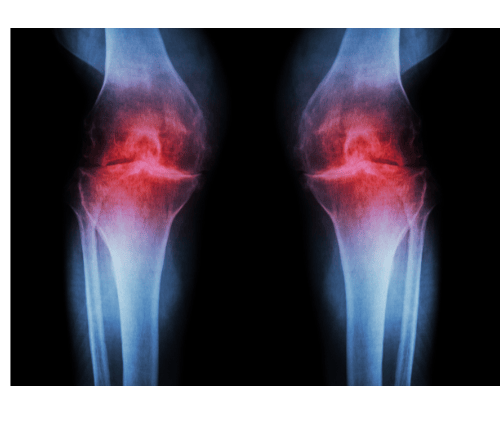

Es la destrucción progresiva del cartílago articular provocada por una interacción de factores de riesgo, estrés mecánico (sobrecarga) y mecánica articular alterada.

Esto genera inicialmente una inflamación articular (mediante marcadores proinflamatorios y proteasas) y finalmente se produce una destrucción del cartílago.

De forma temprana se desarrolla fibrilación superficial, irregularidad y erosiones focales. Estas erosiones eventualmente se extienden hasta el hueso y se expanden continuamente para involucrar una mayor parte de la superficie articular.

Con el tiempo, la matriz de colágeno (proteína del tejido) se daña, los condrocitos (células del cartílago) proliferan y se forman condrocitos hipertróficos, lo que provoca crecimientos anormal de cartílago que se osifican y forman osteofitos (protuberancias óseas). También se genera una inflamación sinovial que puede afectar a tejidos blandos de alrededor: cápsula, ligamentos y meniscos.

Cabe remarcar que NO todas las personas que presentan signos de artrosis en imágenes complementarias (radiografías) tienen porqué presentar síntomas. La degeneración articular es un proceso fisiológico progresivo que se da con la edad. Solo se le ha de dar importancia cuando las imágenes pueden correlacionarse con la clínica.